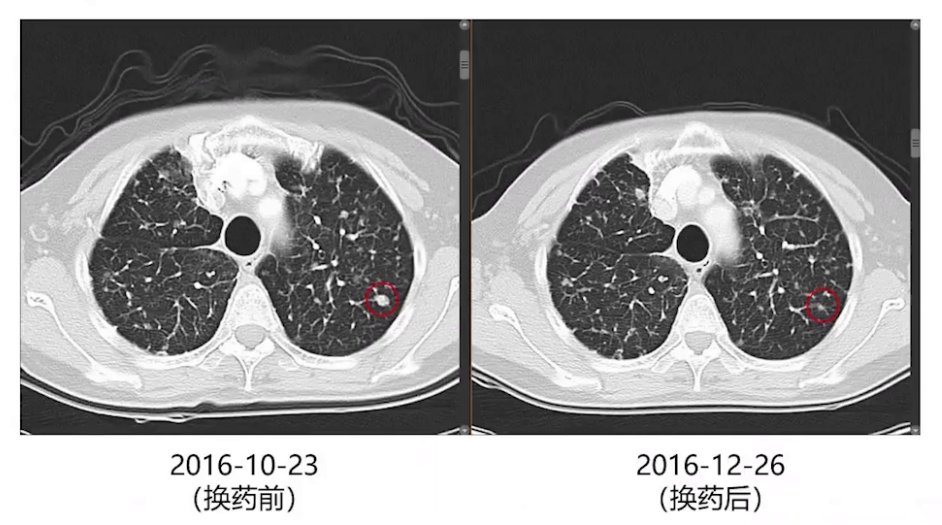

术后3个月、6个月及9个月复查,双肺结节逐渐增大,考虑厄洛替尼耐药,2016年10月改服奥西替尼。两个月后影像复查,双肺增大的结节再次缓解。此后每2-3个月复查胸部增强CT,每半年进行一次全身检查。